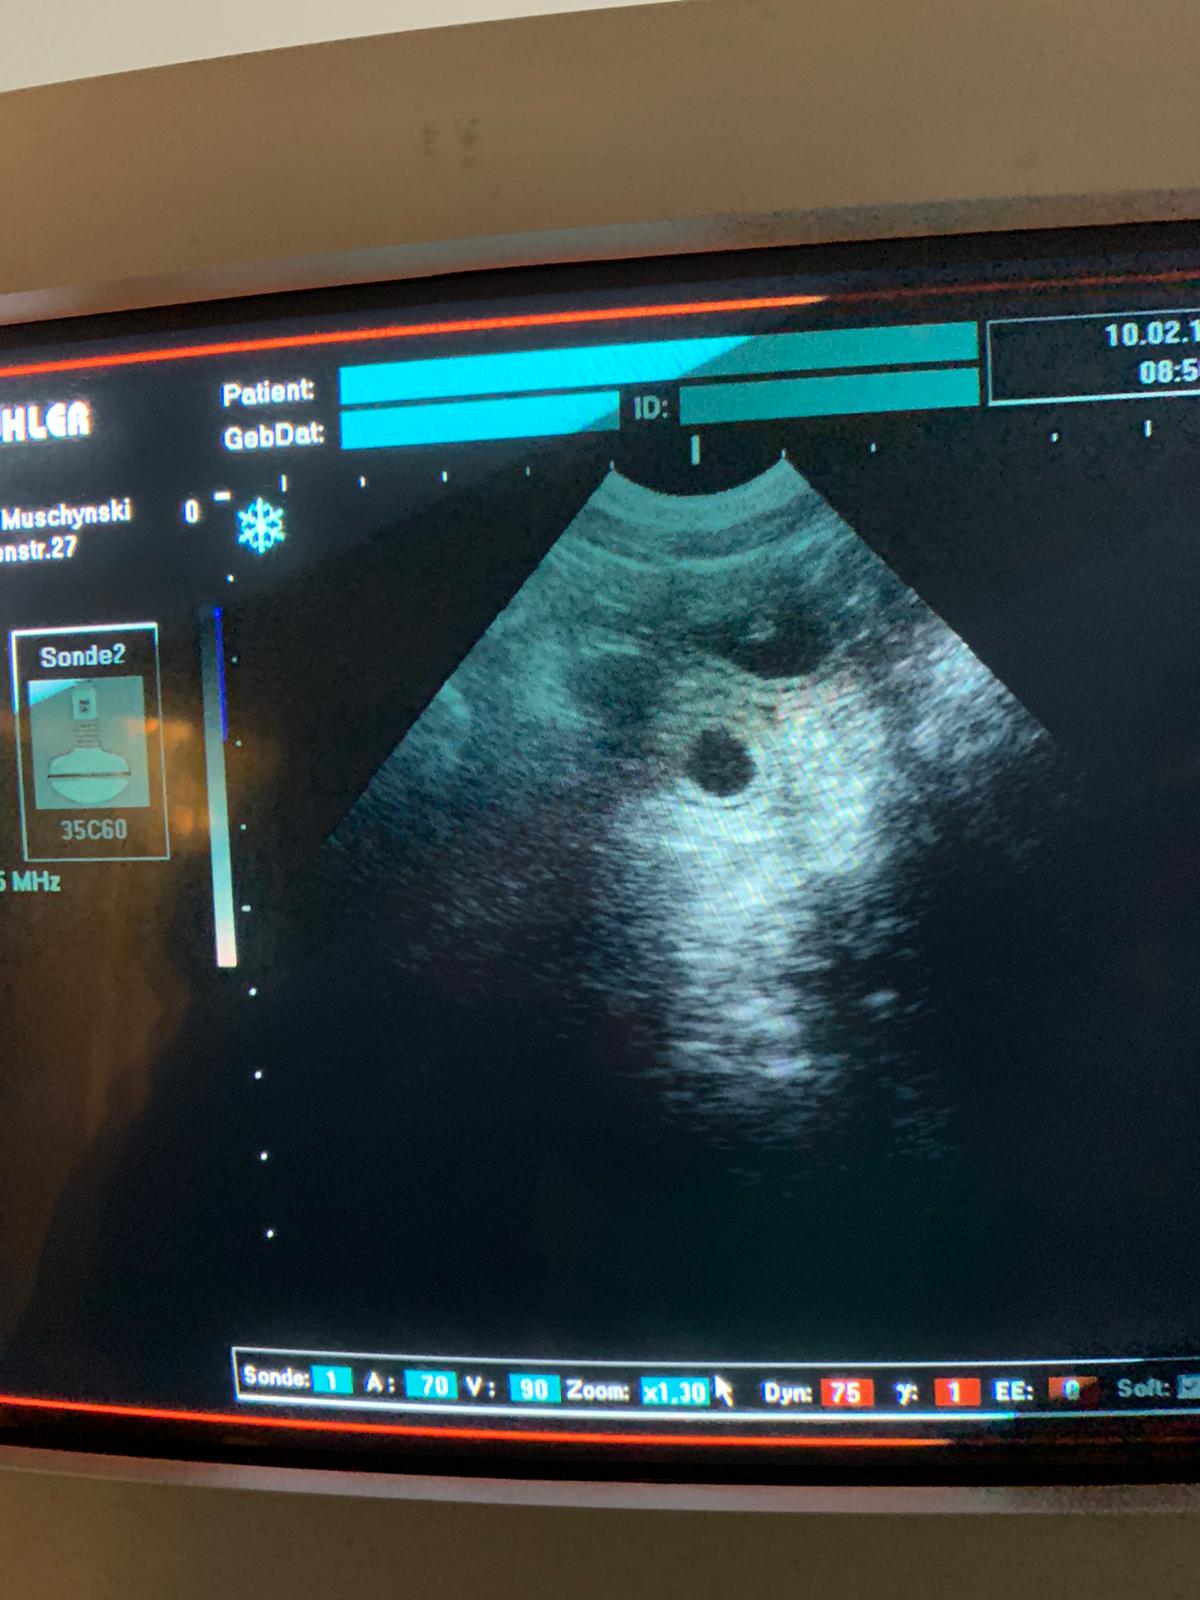

Wir haben die Trächtigkeit bestätigt! Peaches hat uns also nicht an der Nase herum geführt, sondern Recht behalten ...:)